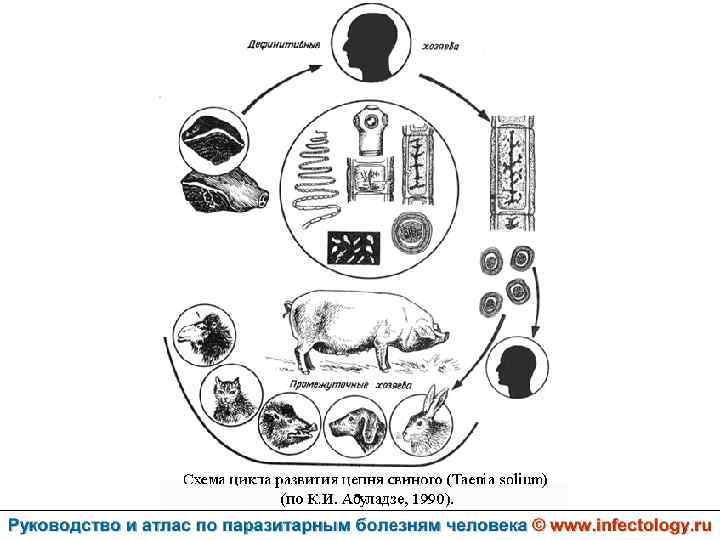

Тениоз (шифр по МКБ 10 - B 68. 0) – антропонозный биогельминтоз, одним из основных клинических проявлений которого является нарушение функций желудочно– кишечного тракта.

Цистицеркоз (шифр по МКБ 10 - B 69) – биогельминтоз, который вызывается паразитированием в тканях и органах человека и животных личиночной стадии цепня вооруженного – цистицерка (Cysticercus cellulosae) Болезнь проявляется разнообразными симптомами в зависимости от локализации цистицерков.